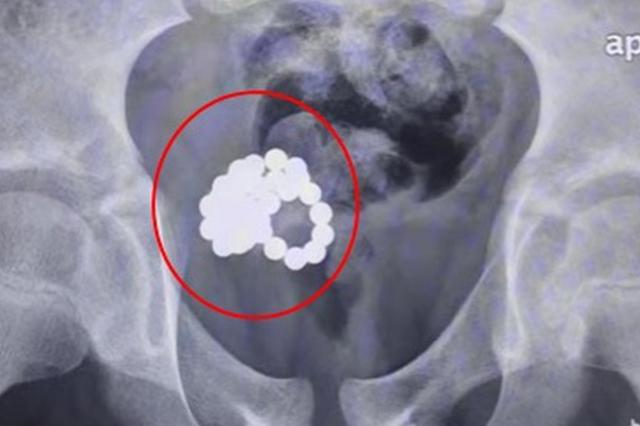

术中拍片提示,尿道中存在大量金属球。由于金属球有磁性,吸在一起,医生们尝试了各种膀胱镜器械均无法取出,最终只能手术取珠,手术共取出了10颗金属磁力珠。未来,这个孩子还有可能面临一系列后遗症。

当医生们还在为这个孩子唏嘘不已的时候,门诊又来了一个同为11岁的男孩。这个男孩如实地讲出了他往尿道里放东西的情况,影像检查显示,孩子的膀胱内有数十颗金属磁力珠吸引在一起。

医生从11岁男童体内取出的磁力珠。上海交大医学院附属新华医院 供图

与前一例情况相似,为了减少手术创伤,医生们尝试了各种微创手段,但却因磁力紧紧吸引,无法成功操作。最终医生只能选择传统手术方式,取出了34颗磁力珠。